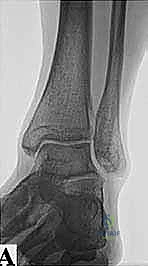

* الأشعة السينية (X-rays): بوضعيات خاصة (Lateral view) لرؤية العظم الزائد (Os Trigonum) والنتوءات العظمية وتضيق المسافات المفصلية.

* التصوير بالرنين المغناطيسي (MRI): هو المعيار الذهبي. يكشف بدقة متناهية عن التهابات الأوتار (مثل FHL)، ارتشاح السوائل، تمزقات الأربطة، ووذمة نخاع العظم (Bone Marrow Edema) التي لا تظهر في الأشعة العادية.

* الأشعة المقطعية (CT Scan): تُستخدم في حالات معينة لعمل خريطة ثلاثية الأبعاد للكسور القديمة أو التكلسات العظمية المعقدة قبل الجراحة.